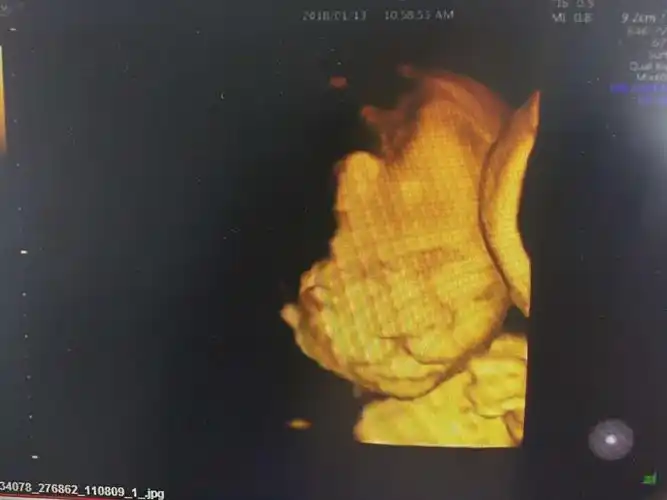

四维照片宝宝这样算兔唇吗

胎儿双侧唇裂四维成像图